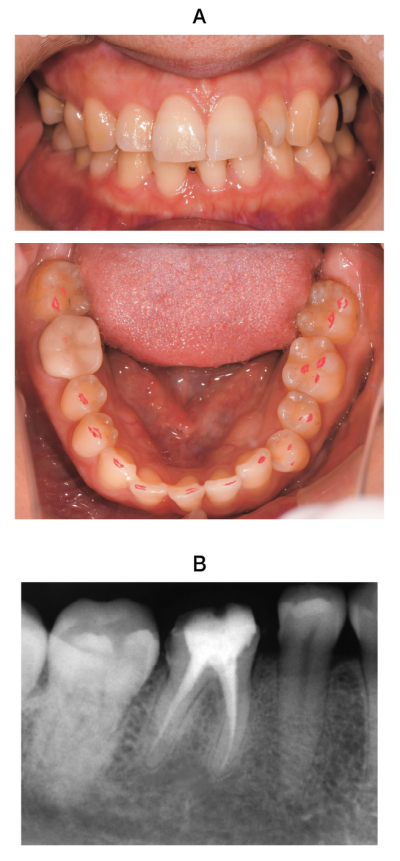

34 歳の女性。下顎右側第一大臼歯部の痛みを主訴として来院した。1年前にクラウンが装着された直後から同部の痛みが発現し、鈍痛が持続しているという。クラウンは除去され、テンポラリークラウン装着後、調整が続けられたが、症状に変化はなかったという。当該歯に打診痛はなく、浸潤麻酔による歯痛の軽減は認めない。右側咬筋部の触診によって歯痛が再現される。4mm 以上の歯周ポケットは認められない。初診時に咬合状態を検査した口腔内写真とエックス線画像を別に示す。

最も疑われるのはどれか。1つ選べ。